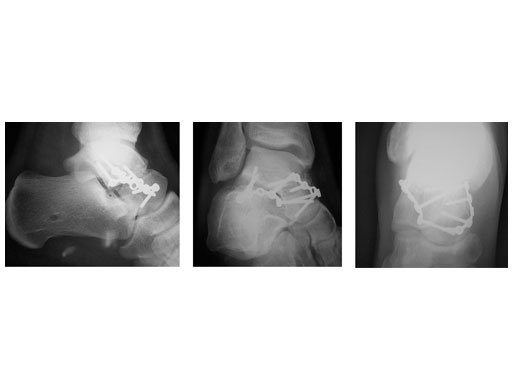

23-year-old male with moto cross accident

Case provided by P. Cronier, Angers, France

ORIF (day 5): Anteromedial approch and Ollier approach